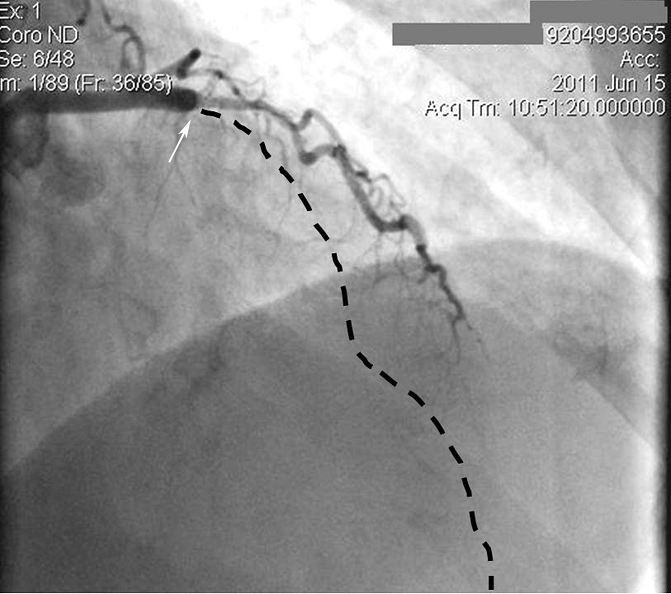

Вот так выглядели артерий сердца после диагностического исследования. Обратите внимание на закупорку главной артерии сердца прямо от начала (показана стрелкой). Ход этой артерии должен быть таким, как показывает пунктирная линия, однако, ее не видно, поскольку из-за закупорки кровь туда не поступает.

А это изображение тех же артерий, но их вид дается с другим углом зрения. Обратите внимание, какой большой участок артерии (пунктирная линия) выключен из кровотока.